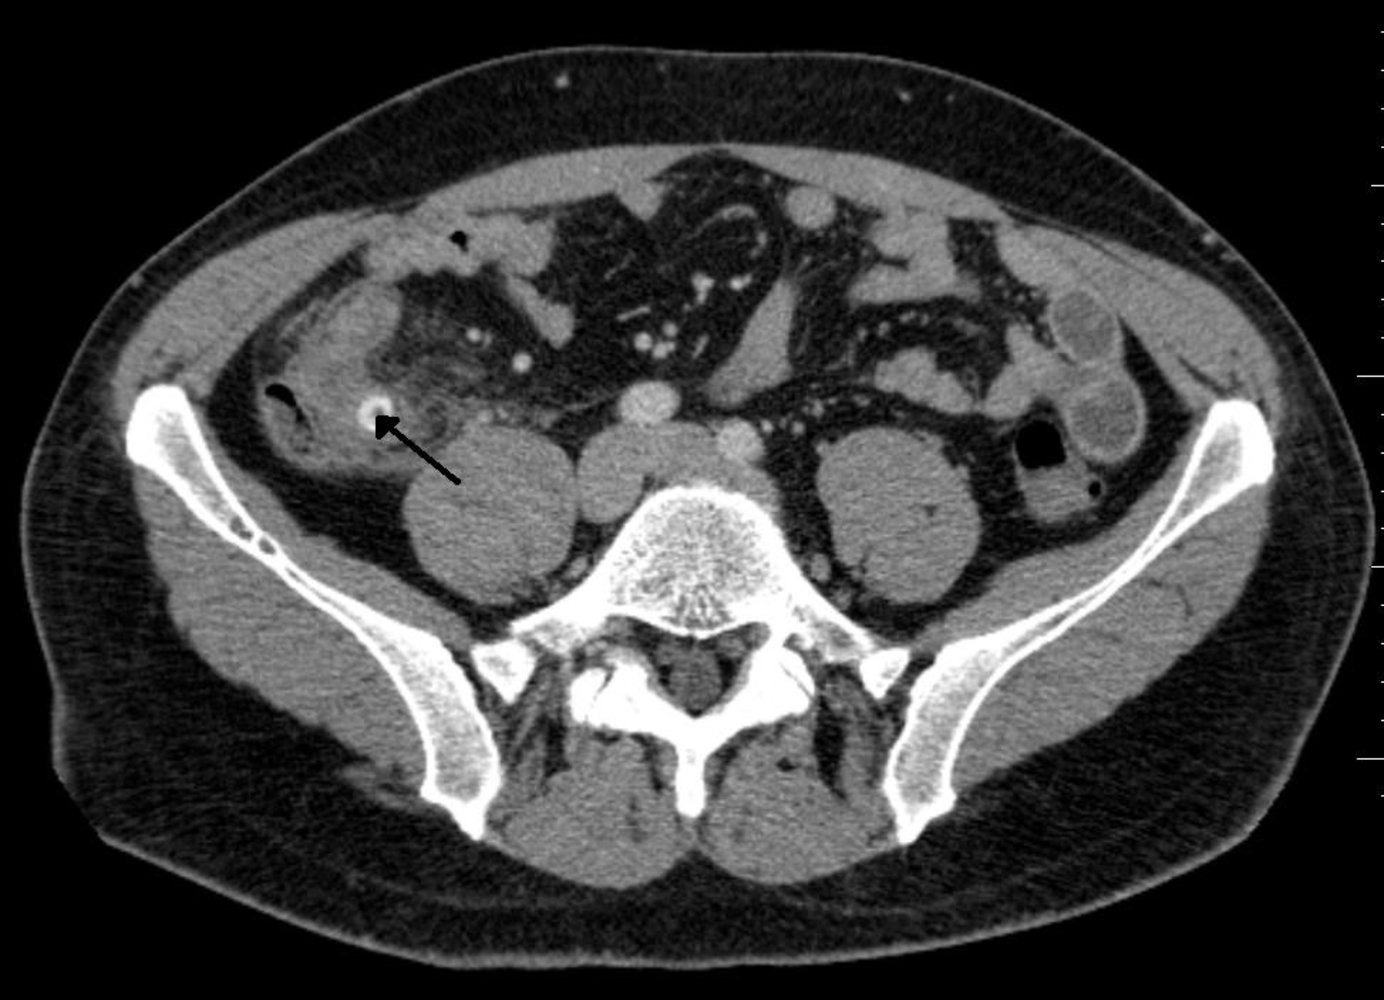

- CT Abdomen/Pelvis (with contrast): Gold standard in adults

- Appendix >6 mm, wall thickening, fat stranding, ± appendicolith